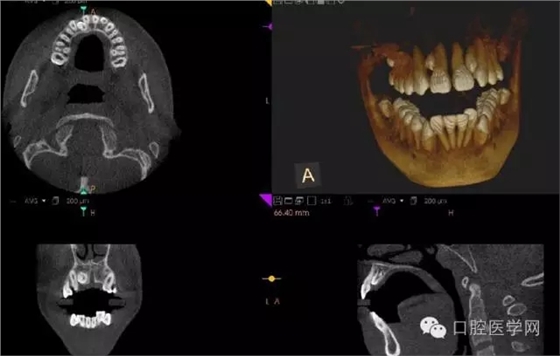

額外牙

X線表現(xiàn):最多見于上頜兩中切牙之間;圓錐形,根短小;拍攝X線片可確定額外牙的數(shù)目、位置、形態(tài)與鄰牙的關(guān)系。